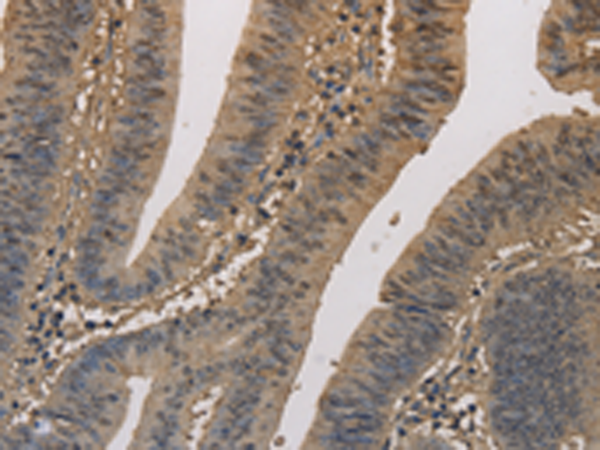

分类: 科研抗体货号: P08266别名: EF2; EF-2; EEF-2; SCA26应用: WB,IHC反应种属: Human, Mouse, Rat